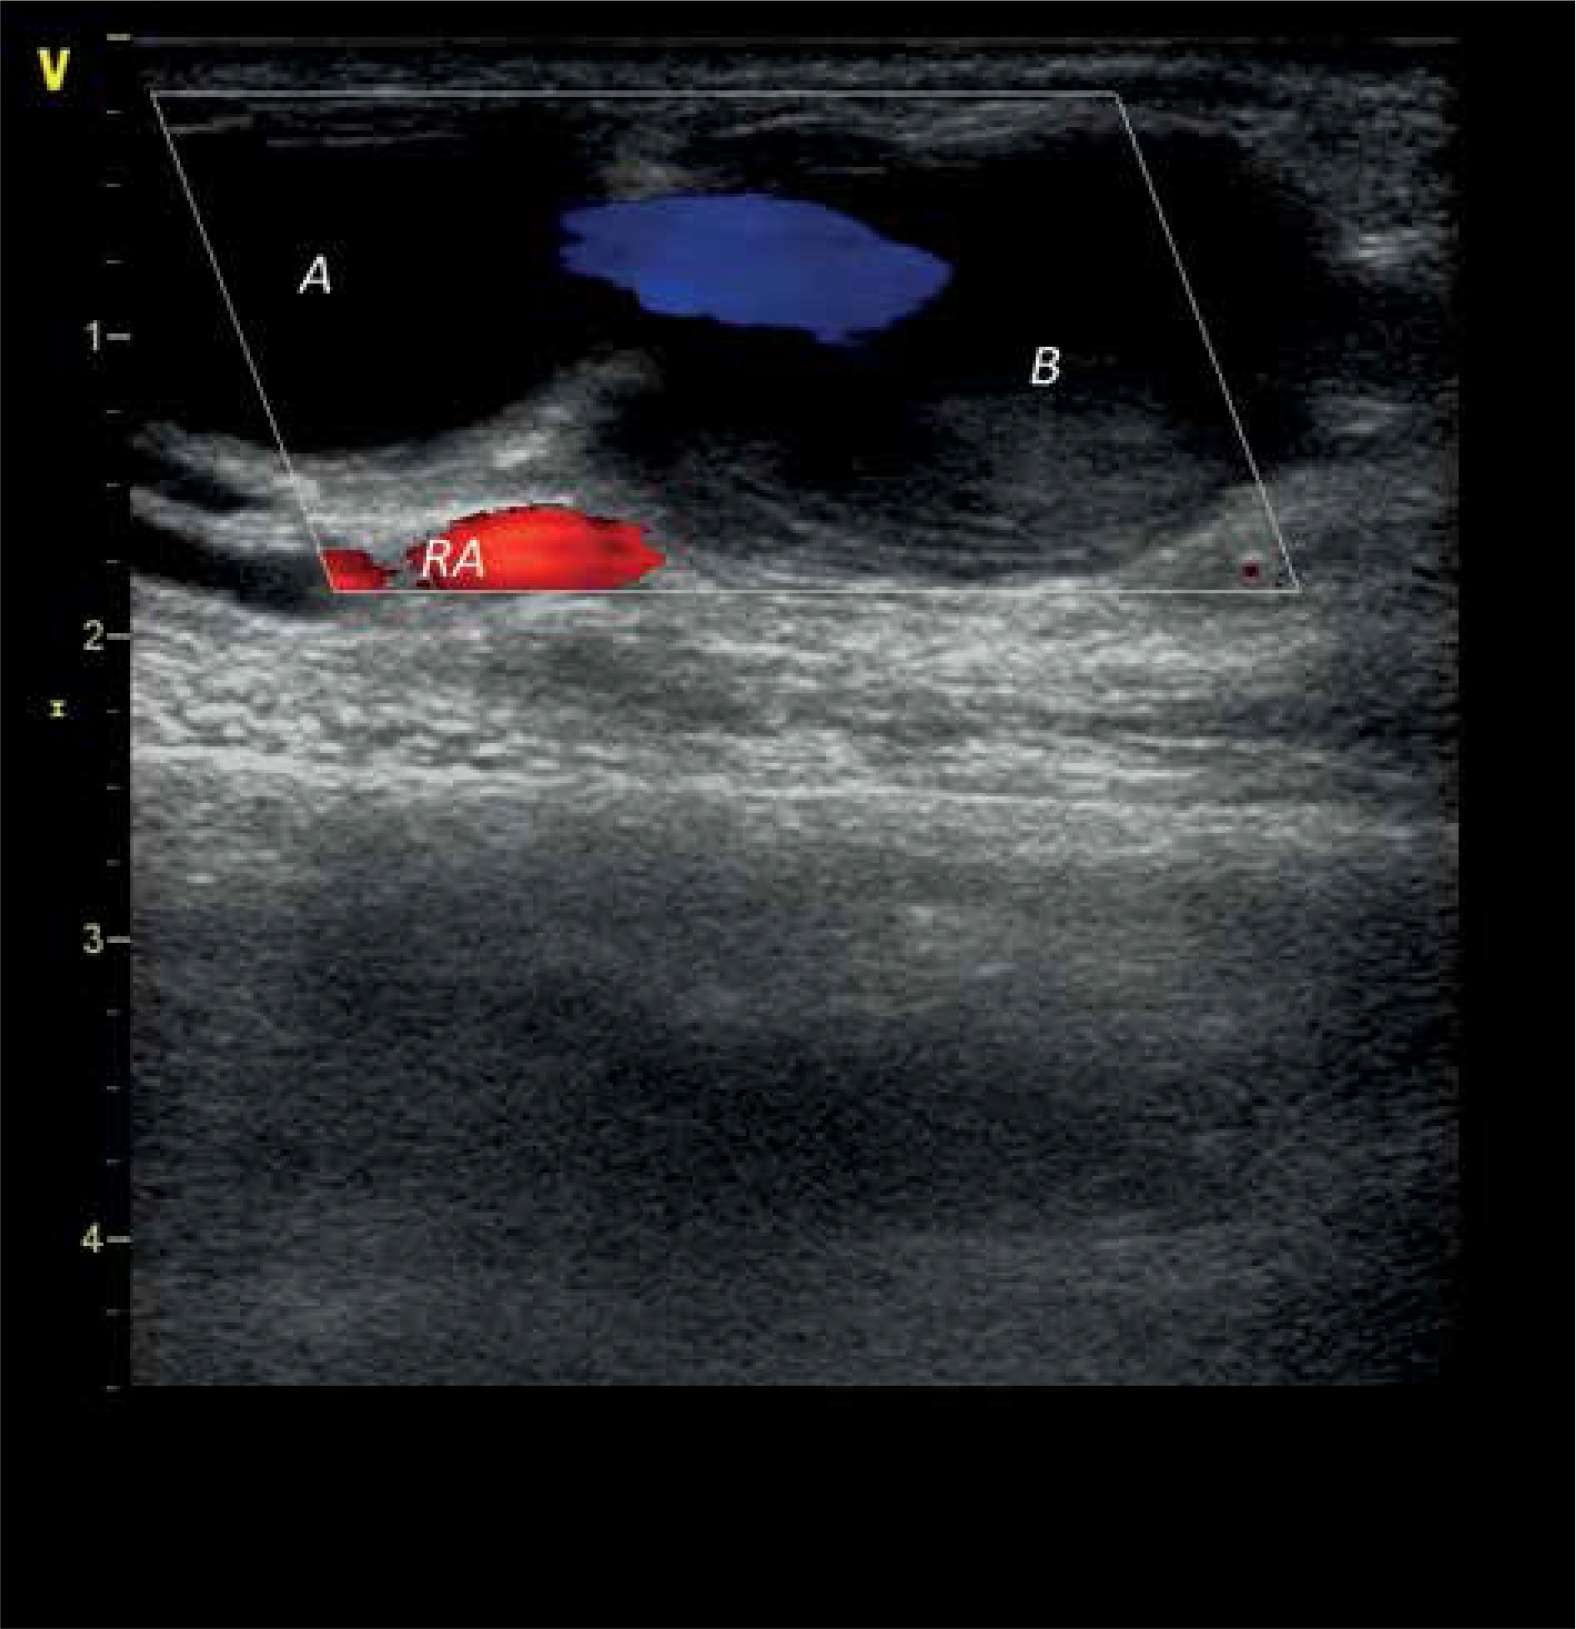

Figure 1

Three successive chambers of the pseudoaneurysm with their dimensions

A – first chamber, B – second chamber, C – third chamber, RA – radial artery.